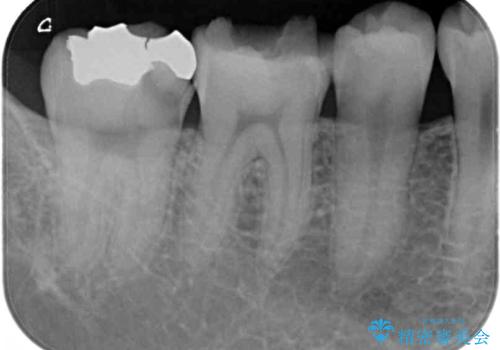

- 右下奥歯の虫歯がしみて痛いとのことで来院された患者様です。

神経近くにまで及ぶ大きな虫歯でしたが、速やかに処置を行い、痛みは即日解消されました。

虫歯が大きかったため、クラウンによる補綴治療が必要になる旨をお伝えしたところ、矯正治療にも興味があるとのことでした。